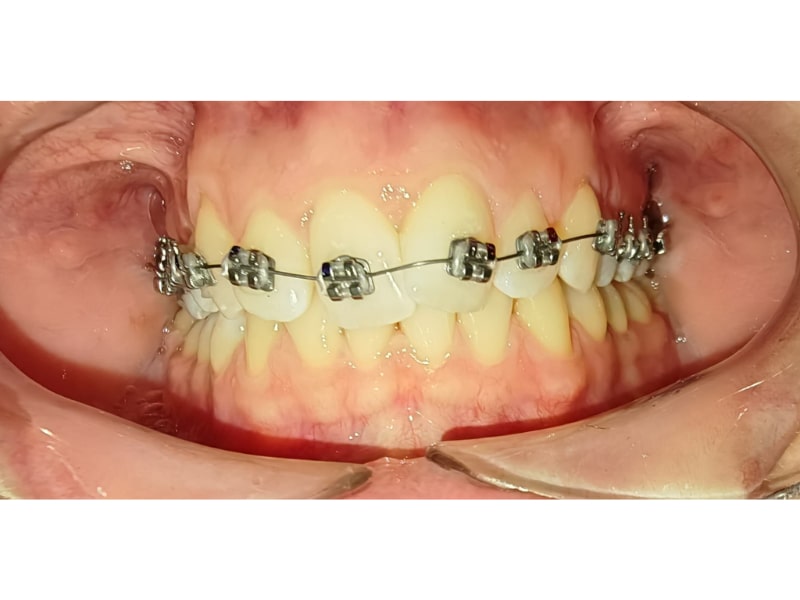

Ortodonție